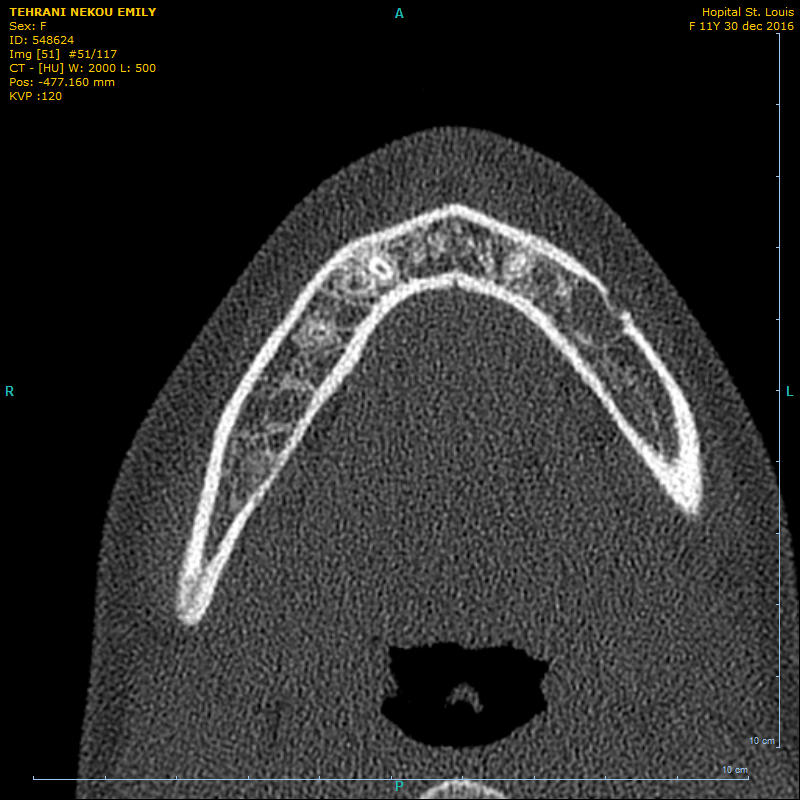

patiente de 11 ans. sans symptôme.au niveau de la 35 apicale, prédence d'une masse hétérogène. vitalité ok.

il n'y a pas de solution de continuité radiologique entre l'espace desmodontal et le périmètre de la lésion qui se superpose à la structure dentaire par un liseré dense.

Je ne crois pas du tout à une lacune de Stafne : trop antérieur et l'image scanner d'une lacune n'a rien à voir. Ca donne normalement une dépression de la table linguale de la mandibule en regard de la glande sous-maxillaire (donc normalement plus postérieur).